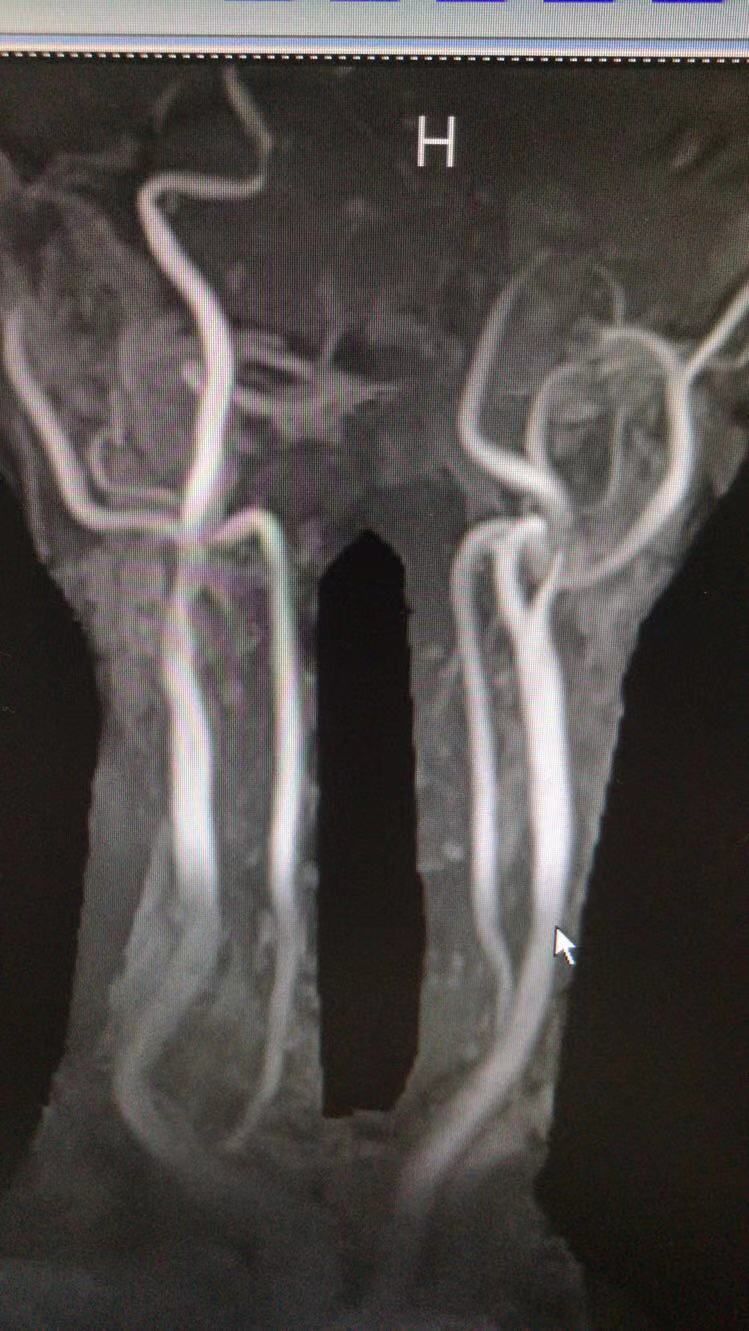

MRA示左侧颈内动脉开口重度狭窄!

左侧颈内动脉供血区显影差!